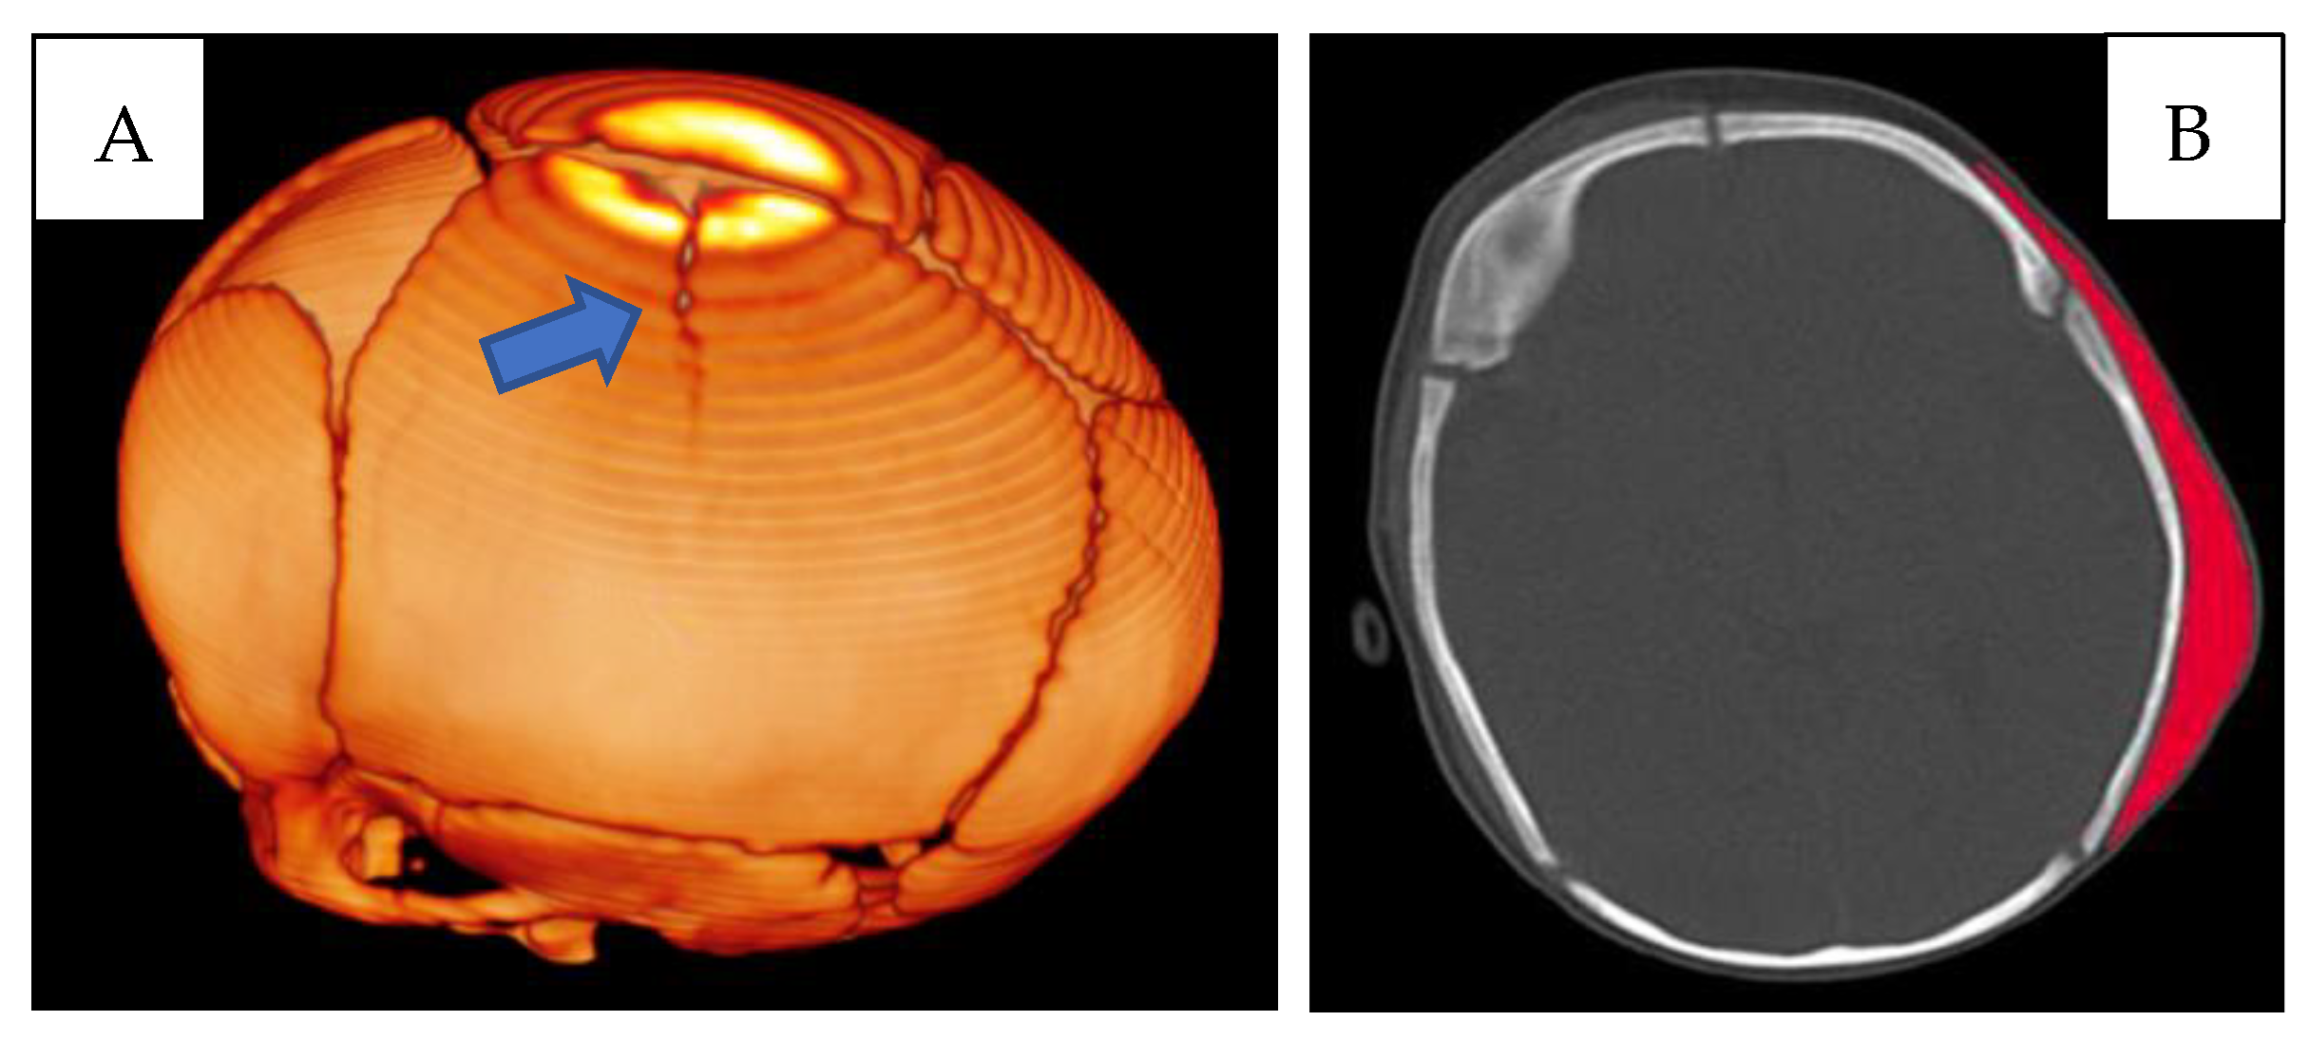

First lesion complex (Figure 1) at the level of the left parietal bone, presence of a cranial fracture with a linear course, starting from the sagittal suture, with craniocaudal direction. Extensive subgaleal haematoma in the parieto-occipital area.

Figure 1. (A) CT skull—3D reconstruction: fracture with a linear course in the left parietal location (blue arrow). (B) CT skull, subgaleal haematoma in the parieto-occipital site (red).